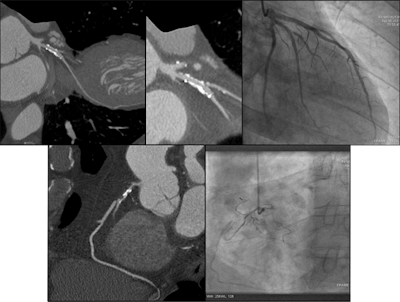

Comparison images demonstrating how high-definition CTA improved reporting accuracy. The case is of a 49-year-old man with previous stent to the circumflex artery with recurrent pain. New scanner technology allows the use of CTCA in patients with known existing heart disease. This is not possible with a conventional CT scanner. This means the interventional cardiologist has all the required information to plan the subsequent intervention. Top left image shows a stent in the circumflex artery but no stenosis. Bottom left shows an occluded right coronary. Top middle also is of the circumflex but demonstrates how the use of the Discovery CT750 HD scanner (GE Healthcare) allows clear visualization of the short stenosis, despite the stent and high level of calcium in the arteries. Top right is a conventional left coronary angiogram confirming the CT findings. Bottom right is the right coronary angiogram confirming findings. All images courtesy of Dr. Carl Roobottom.Having conducted an audit of their service for rate and cause of nondiagnosis in 2009, the Plymouth researchers decided to carry out a reaudit. All attendees for coronary CTA (CCTA) examinations for the investigation of coronary artery disease during a three-month period were reviewed. The analysis included 329 patients, and the cohort was similar to the original one, although it was older (59 versus 61 years) and with higher body mass indices.